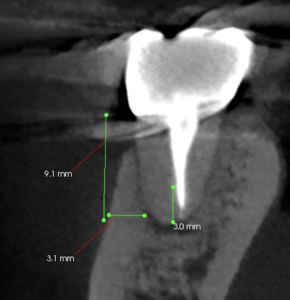

頬側の歯槽骨を厚く(3mm), Osteotomyしなければならない。

当該部位をOsteotomyするが…

3mm削合してもApexが出てこなかった。

私はこの際、咄嗟に患者さんの頭の位置を真横に向けてもらうようにした。

私が当たりをつけた位置は出鱈目な場所であった。。。

Osteotomyする際は必ず歯牙の真正面に位置取りをしなければならない